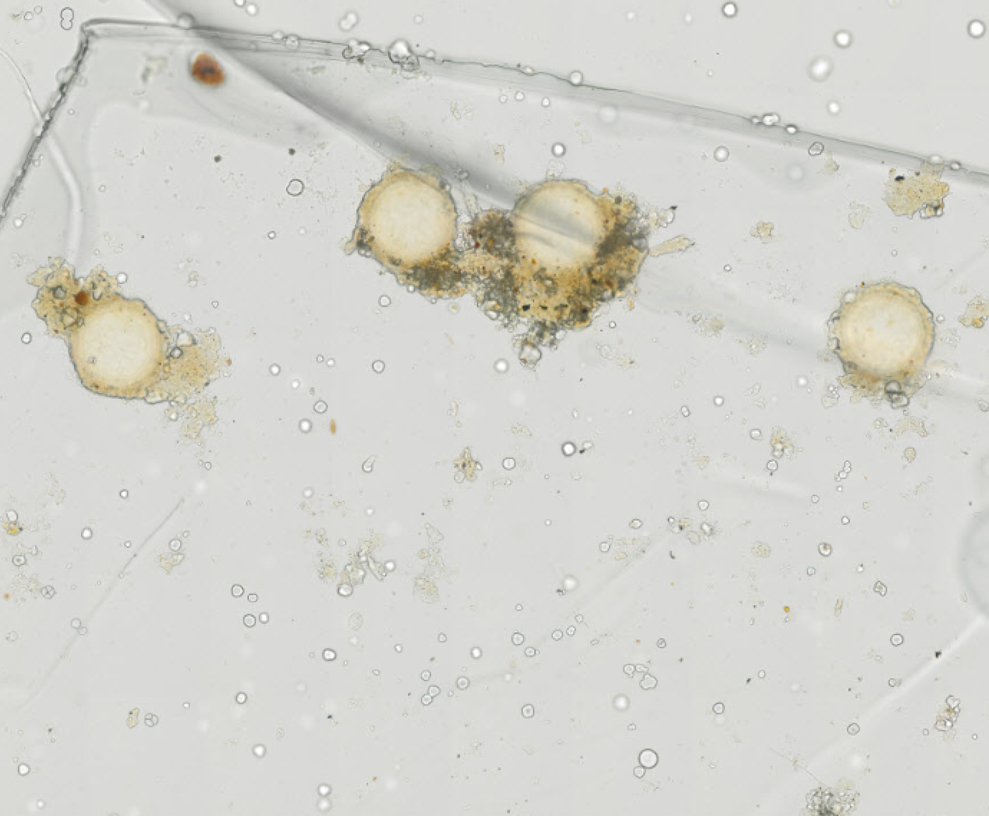

Echinococcus granulosus - Tasiemiec bąblowcowy - Protoskoleksy z torbieli bąblowcowej

Echinococcus multilocularis - Tasiemiec wielojamowy - Torbiel z protoskoleksami